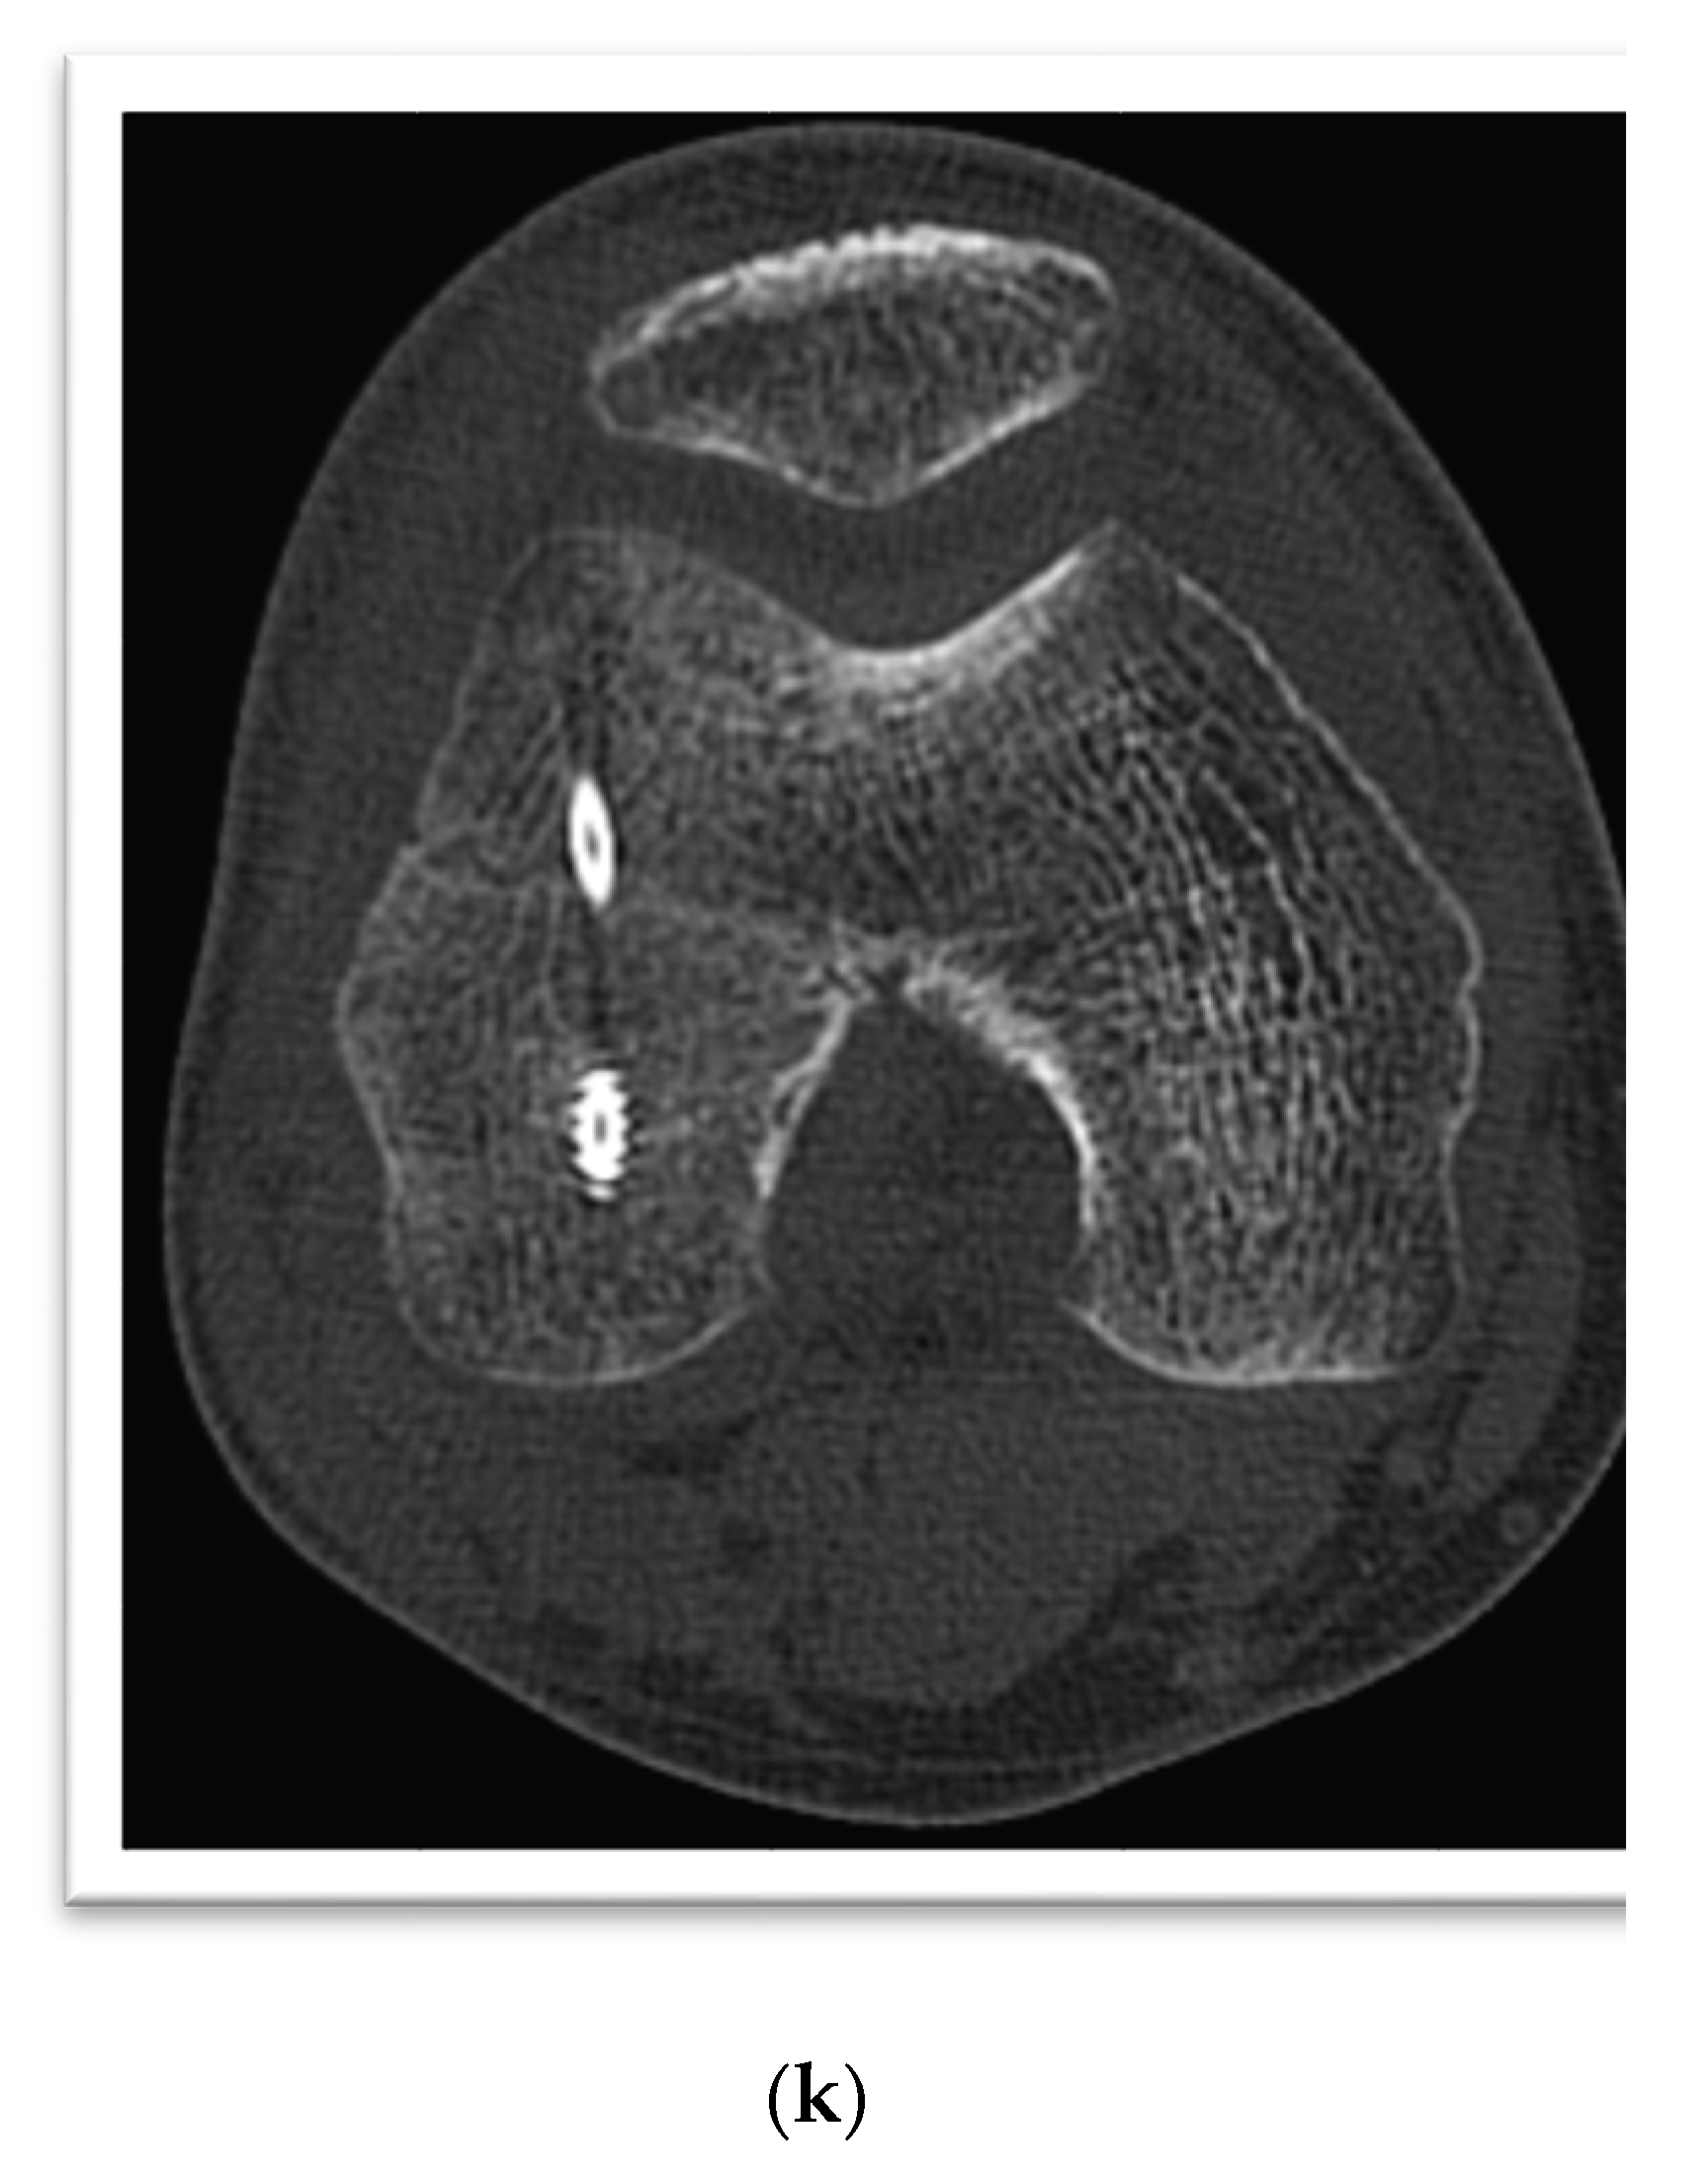

3. Case Presentation

4. Case Presentation

5. Case Presentation